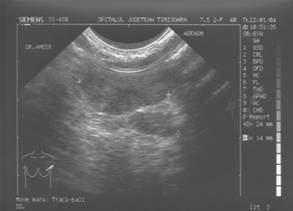

Tumorile si pseudotumorile sanului sunt patologii frecvente, dominate mai ales de fibroadenom, care este o patologie obisnuita la femeie tanara.

De fiecare data cand persista o indoiala asupra unei formatiuni solide, ca de ex. un „fibroadenom” aparut la o femeie in varsta, nu trebuie sa se ezite la a recurge la tehnici interventionale, si anume microbiopsii ghidate imagistic, pentru a nu lasa sa evolueze un carcinom cu aspect rotund.